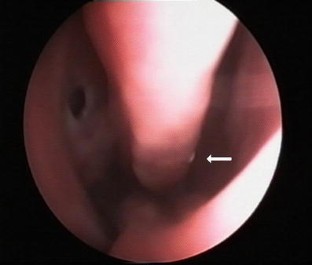

We report a case of human nasal myiasis caused by fruit fly larvae in a 33-year-old man who visited the south coast of Turkey. The fruit fly (Drosophila melanogaster) is endemic in the southern part of Turkey. Infestation with fruit fly larvae must be considered in patients who are visiting areas of the world where Drosophila is endemic. This is the first reported case of fruit fly larvae causing human nasal myiasis. The clinical presentation and treatment strategies are discussed.

Fig. 1